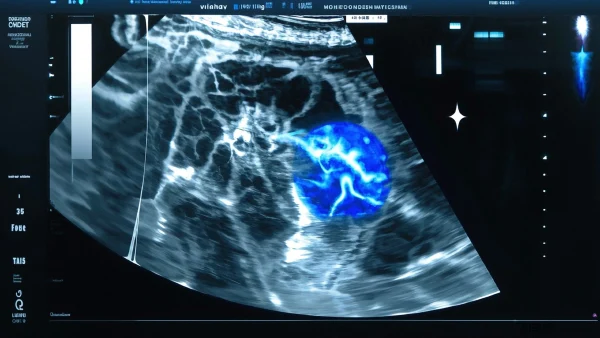

03 超声下的胆囊炎长啥样?

医学界普遍认同超声是检测胆囊疾病的首选技术(Trowbridge et al., 2003)。超声波就像医生手中的“透视眼”,帮我们发现肉眼看不到的内部变化。遇到胆囊炎,超声常见这些信号—

- 胆囊壁变厚:稍微超过3毫米(约等于一枚硬币的厚度),通常说明有炎症。

- 胆囊腔内有结石:回声强、伴声影,像“小石子”卡在胆囊中。

- 胆囊周围液体:出现异常积液时,可能炎症波及周围组织。

- 胆囊收缩差:吃完饭后仍未“变瘦”,说明功能受影响。

👨🏻⚕️ 有位58岁女性,因饭后右上腹持续胀痛就诊。B超发现:胆囊壁局部明显变厚,内见数粒结石。这个例子提醒我们,超声下的小改变,往往就是早期报警信号。

💡 胆囊壁增厚≠胆囊炎,但结合症状和超声其它特点,能大大提高早期发现率。